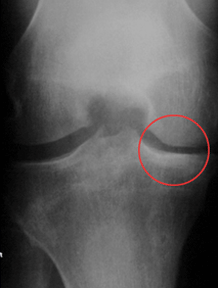

Review of x-rays revealed narrowing of the medial joint space of his right knee and a small amount of osteophyte formation.

Review of his knee x-ray (left - from the front) demonstrated varus deformity, however there was some preservation of the medial joint space (circled - compare with pre-op above).